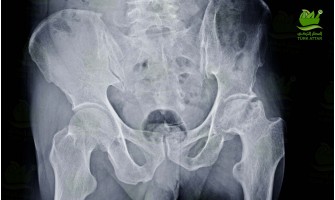

01 Dec Avascular Necrosis

Avascular necrosis is most common in the hip joint. The blood circulation in the vessels feeding the femoral head stops and the bone under the articul..